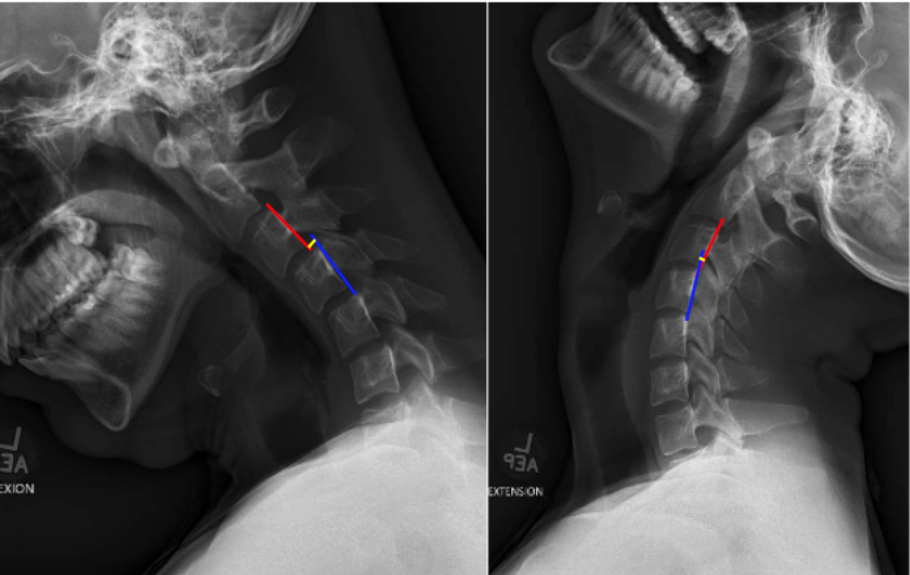

C2–C7 Translation quantifies the anterior–posterior (A–P) displacement of the cervical vertebrae between flexion and extension positions.

The measurement encompasses translation between vertebral bodies at each motion segment (C2–C7) during physiological flexion and extension.

• Obtain lateral cervical spine X-rays in both full flexion and full extension, ensuring visualization from C2 to C7.

• Identify the vertebral levels to assess (typically C2–C3 through C6–C7).

• For each motion segment:

• Draw a vertical line along the posterior vertebral body margin of the superior vertebra (e.g., C4).

• Draw a corresponding line along the posterior vertebral body margin of the adjacent inferior vertebra (e.g., C5).

• Measure the horizontal (anterior–posterior) distance between these lines in flexion and extension views.Calculate translation as the difference between flexion and extension positions.

• Record the translation value for each segment (in millimeters).The largest measured translation among segments (typically C4–C5 or C5–C6) is reported as the maximum translational motion.